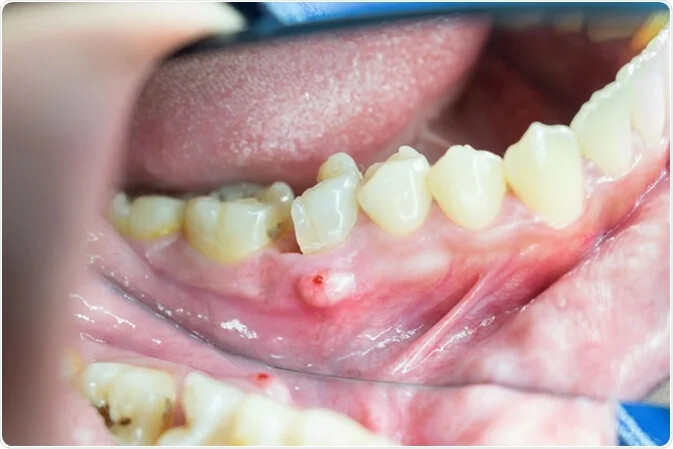

A dental abscess is your body's inflammatory reaction to an infection in the tooth's nerve. The abscess itself is a collection of pus arising from a source of infection at the tooth's root, which can break through the tissues and discharge into the mouth.

Pus and swelling of surrounding tissues